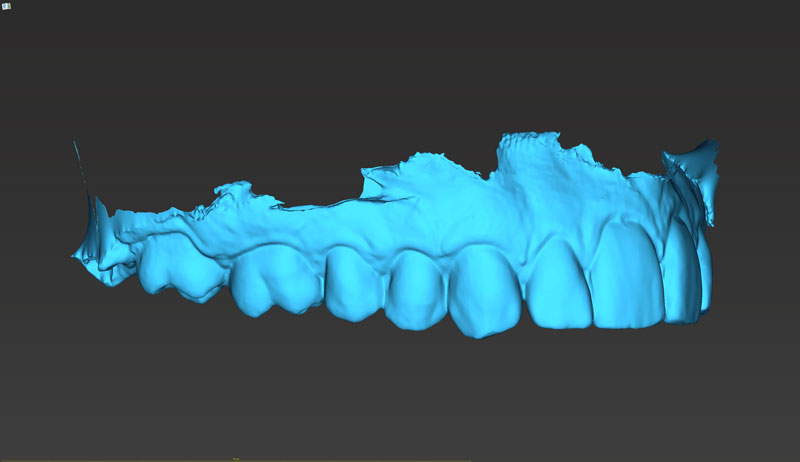

Σχεδιασμός χειρουργικού οδηγού

Κατασκευή χειρουργικού οδηγού στο ιατρείο (3d printing)